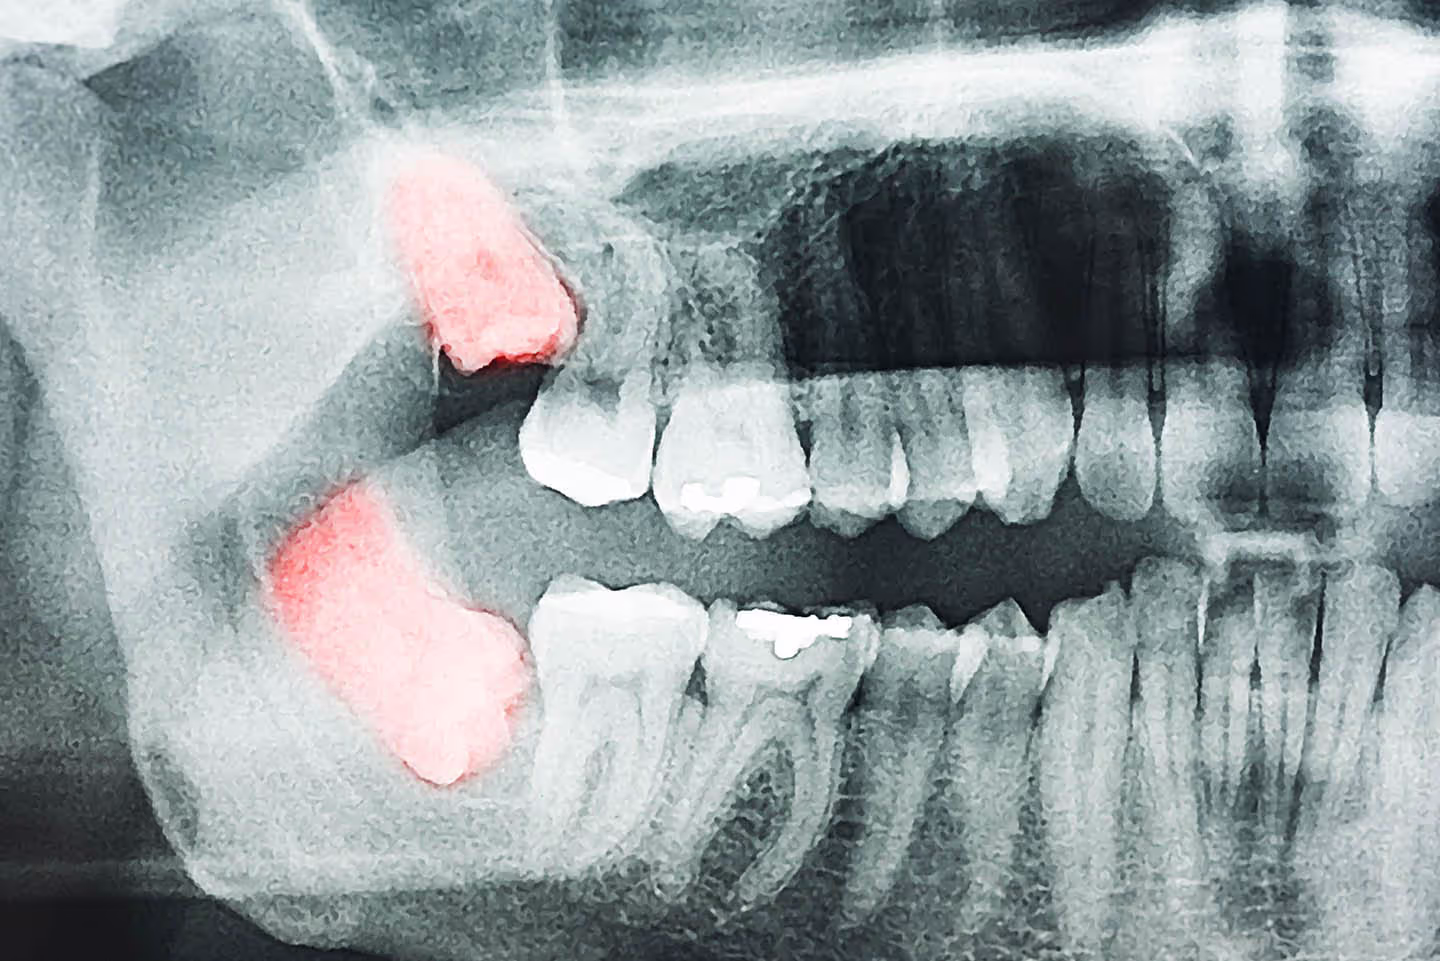

Dental x-rays